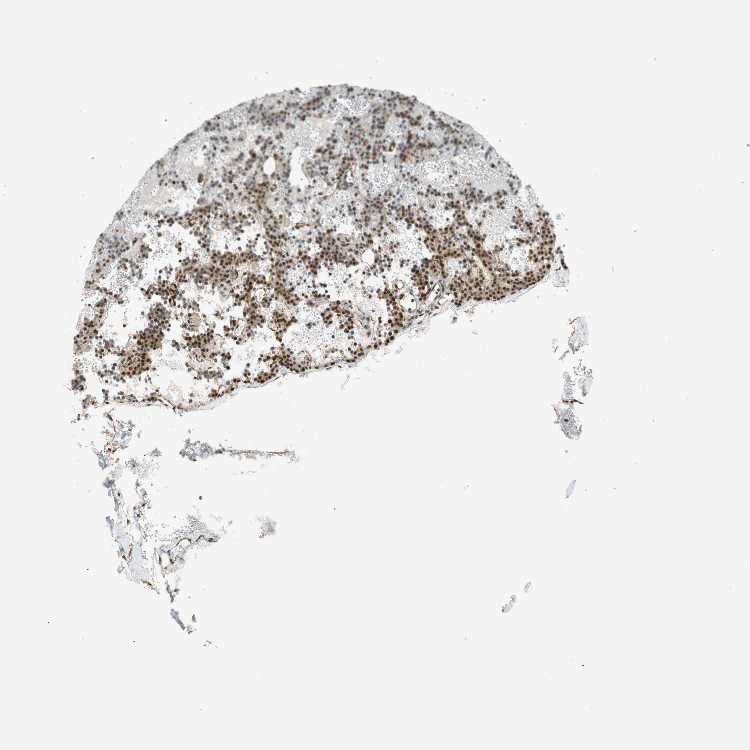

PARATHYROID GLAND - Antibody stainingi

Antibody staining in the annotated cell types in the current human tissue is reported as not detected, low, medium, or high, based on conventional immunohistochemistry profiling in selected tissues. This score is based on the combination of the staining intensity and fraction of stained cells.

Each image is clickable and will lead to virtual microscopy that enables deeper exploration of all samples and also displays staining intensity scores, fraction scores and subcellular localization as well as patient and tissue information for each sample.

Antibody HPA007007Antibody HPA026111Antibody CAB005889Antibody CAB058692

Glandular cells Not detectedNot detectedMediumNot detected